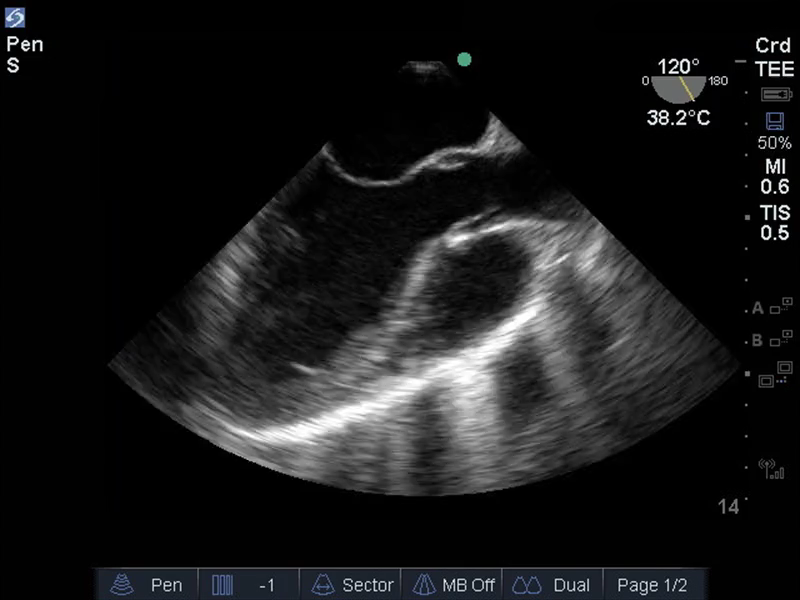

TEE食道中位長軸の画像